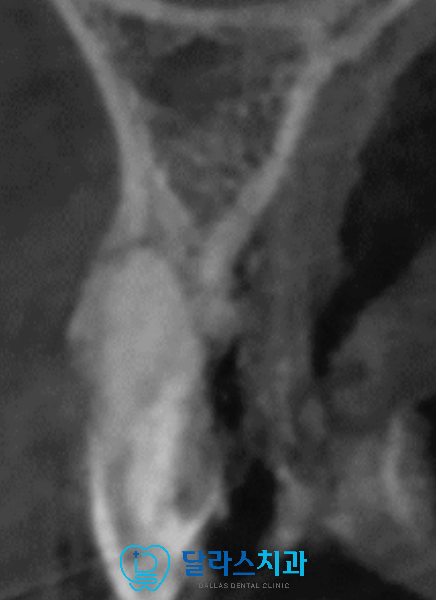

x-ray를 통해 정밀하게 진단을 진행한 결과

해당 부위에는 낭종이 관찰되어 정확한 상태를 알기 위해

입체적인 CT를 촬영해보았습니다.

이미 치아 주변으로는 치조골이 상당히 얇아져있어서

치아의 앞쪽으로 거의 붙어있었고 큰 낭종이 생겨있는 상태여서

이 부위를 모두 제거한다고 해도

일반적인 방법으로는 임플란트 식립이 어려운 상황이었습니다.